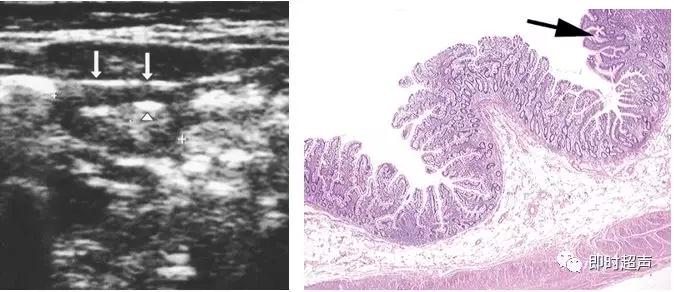

梅克尔憩室超声声像图

梅克尔憩室患者右下腹超声声像图 可见一段增厚管

状肠袢样结构,黏膜较正常小肠黏膜明显增厚